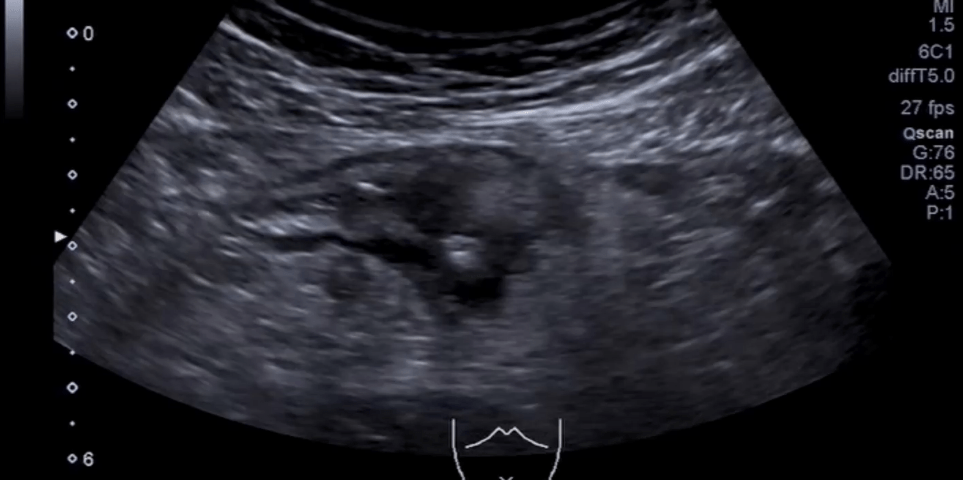

Student Image Challenge #109

Case:   The 42-year-old patient presented to the emergency room with severe, cramp-like pain in her lower left abdomen that had been present for 24 hours, accompanied by a fever of up to 38.8°C, mild nausea, and changes in stool frequency.

What is the diagnosis?